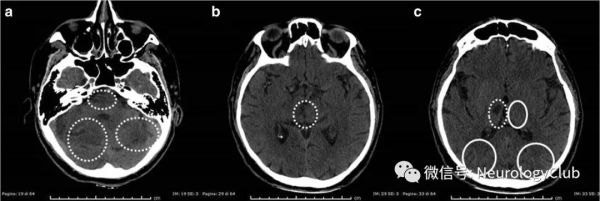

Alberta卒中项目早期CT评分(Alberta stroke program early CT score,ASPECTS)是量化早期CT缺血变化的系统方法,其评估卒中严重程度的临床效益与NIHSS评分相当。pc-ASPECTS可快速评估后循环卒中患者早期缺血性变化(从出现症状不超过3小时)及后循环卒中的进展并预测PCI的结局,有助于PCI患者早期复苏和溶栓治疗。pc-ASPECTS评分分值从10分到0分,正常的CT扫描的相位值为10分,中脑或脑桥存在局部缺血,则各减2分;左侧或右侧丘脑、小脑、大脑后动脉区域有缺血灶,各减1分;0分表示大脑中动脉范围内弥漫性缺血;pc-ASPECTS评分≤7是单变量和多变量模型中不良结果最强的预测因子。Caruso等发现在后循环卒中急性期使用扩展神经成像方案(CT/CTA-SI/CTP结合pc-ASPECT)具有较高的敏感性,结果显示CT,CT+CTA计算的pc-ASPECT得分敏感性均为24%,CT+CTA+CTP计算的pc-ASPECT得分敏感性为72%,该方案可能成为医生的PCI诊断和实际预后评估工具。Lin等还发现pc-ASPECTS和基线NIHSS的组合模型对预测PCI结果具有相加效应,因为pc-ASPECTS在检测NIHSS评分为0-1的PCI不良结果时更有效。

(插图1:入急诊室昏迷患者的后循环ASPECT[pc-ASPECT];后循环ASPECT从10分开始计算,如果在脑桥或中脑中发现缺血,减2分,而小脑、大脑后动脉区域和单个丘脑钟发现缺血,则减1分;本例中,虚线圆圈表示受累区域,连续圆圈表示未受累区域,故pc-ASPECT为3分;引自:Sparaco M, Ciolli L, Zini A. Posterior circulation ischemic stroke-a review part II: imaging and acute treatment. Neurol Sci. 2019 Oct;40(10):2007-2015.)